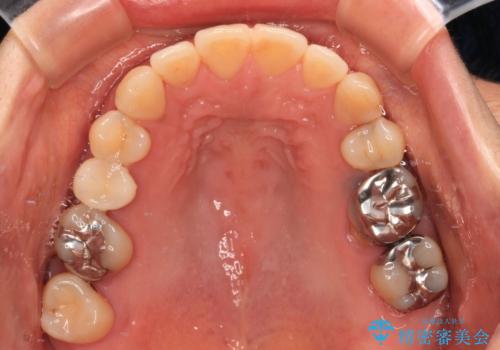

- 飛び出した上顎前歯と正中のズレを気にして来院された患者様です。

上顎正中が右側にずれていたので、むし歯が酷く抜歯が必要な左側臼歯を抜歯して正中を改善することとしました。

左下には新しいセラミックのブリッジが装着されていたため、ブリッジを壊さずに改善できるところまで咬み合わせを改善していくこととしました。

右上小臼歯は銀歯が装着されており、ワイヤー矯正の装置が装着できないため、事前に仮歯に変えてから矯正治療を行い、その後オールセラミッククラウンにて補綴治療を行いました。